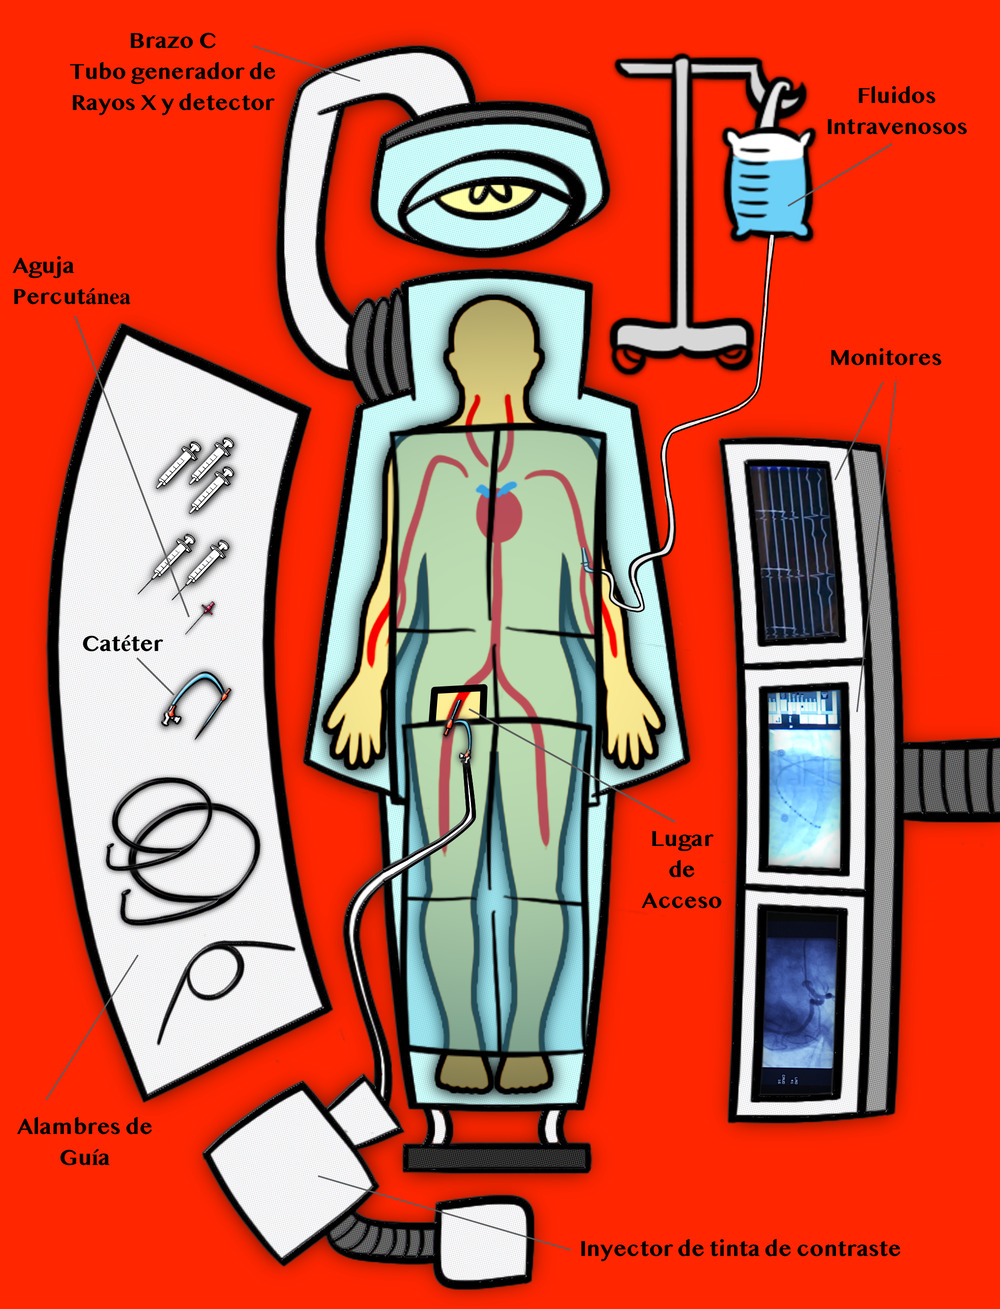

El día antes del cateterismo, recibes una llamada de la enfermera para revisar qué medicamentos tomas. También te dirá qué traer el día del procedimiento. Cuando llegues para tu cateterismo, el equipo del laboratorio te coloca sobre la mesa, te conecta al monitor cardiaco y se asegura de que tu vía intravenosa esté funcionando. Recibirás medicamentos que te ayudarán a relajarte y tal vez hasta dormir durante la cateterización. Pero no te sorprendas si te quedas despierto; esto no es inusual. Se adormece el lugar en donde se insertará el catéter. Esto se hace inyectando medicamentos en el área usando una jeringuilla. Una vez esté insensibilizada el área se usa una aguja para llegar a una de tus arterias. Una vez la jeringuilla está dentro de la arteria, se remplaza con un tipo de envoltura. Esta envoltura será la entrada principal hacia tu cuerpo. Todo lo que el doctor necesita para estudiar y tratar tu corazón entra a través de la envoltura. Luego entra el catéter. Viajará por las arterias de tu cuerpo hasta tu corazón; esto, desde esa misma pequeña incisión.